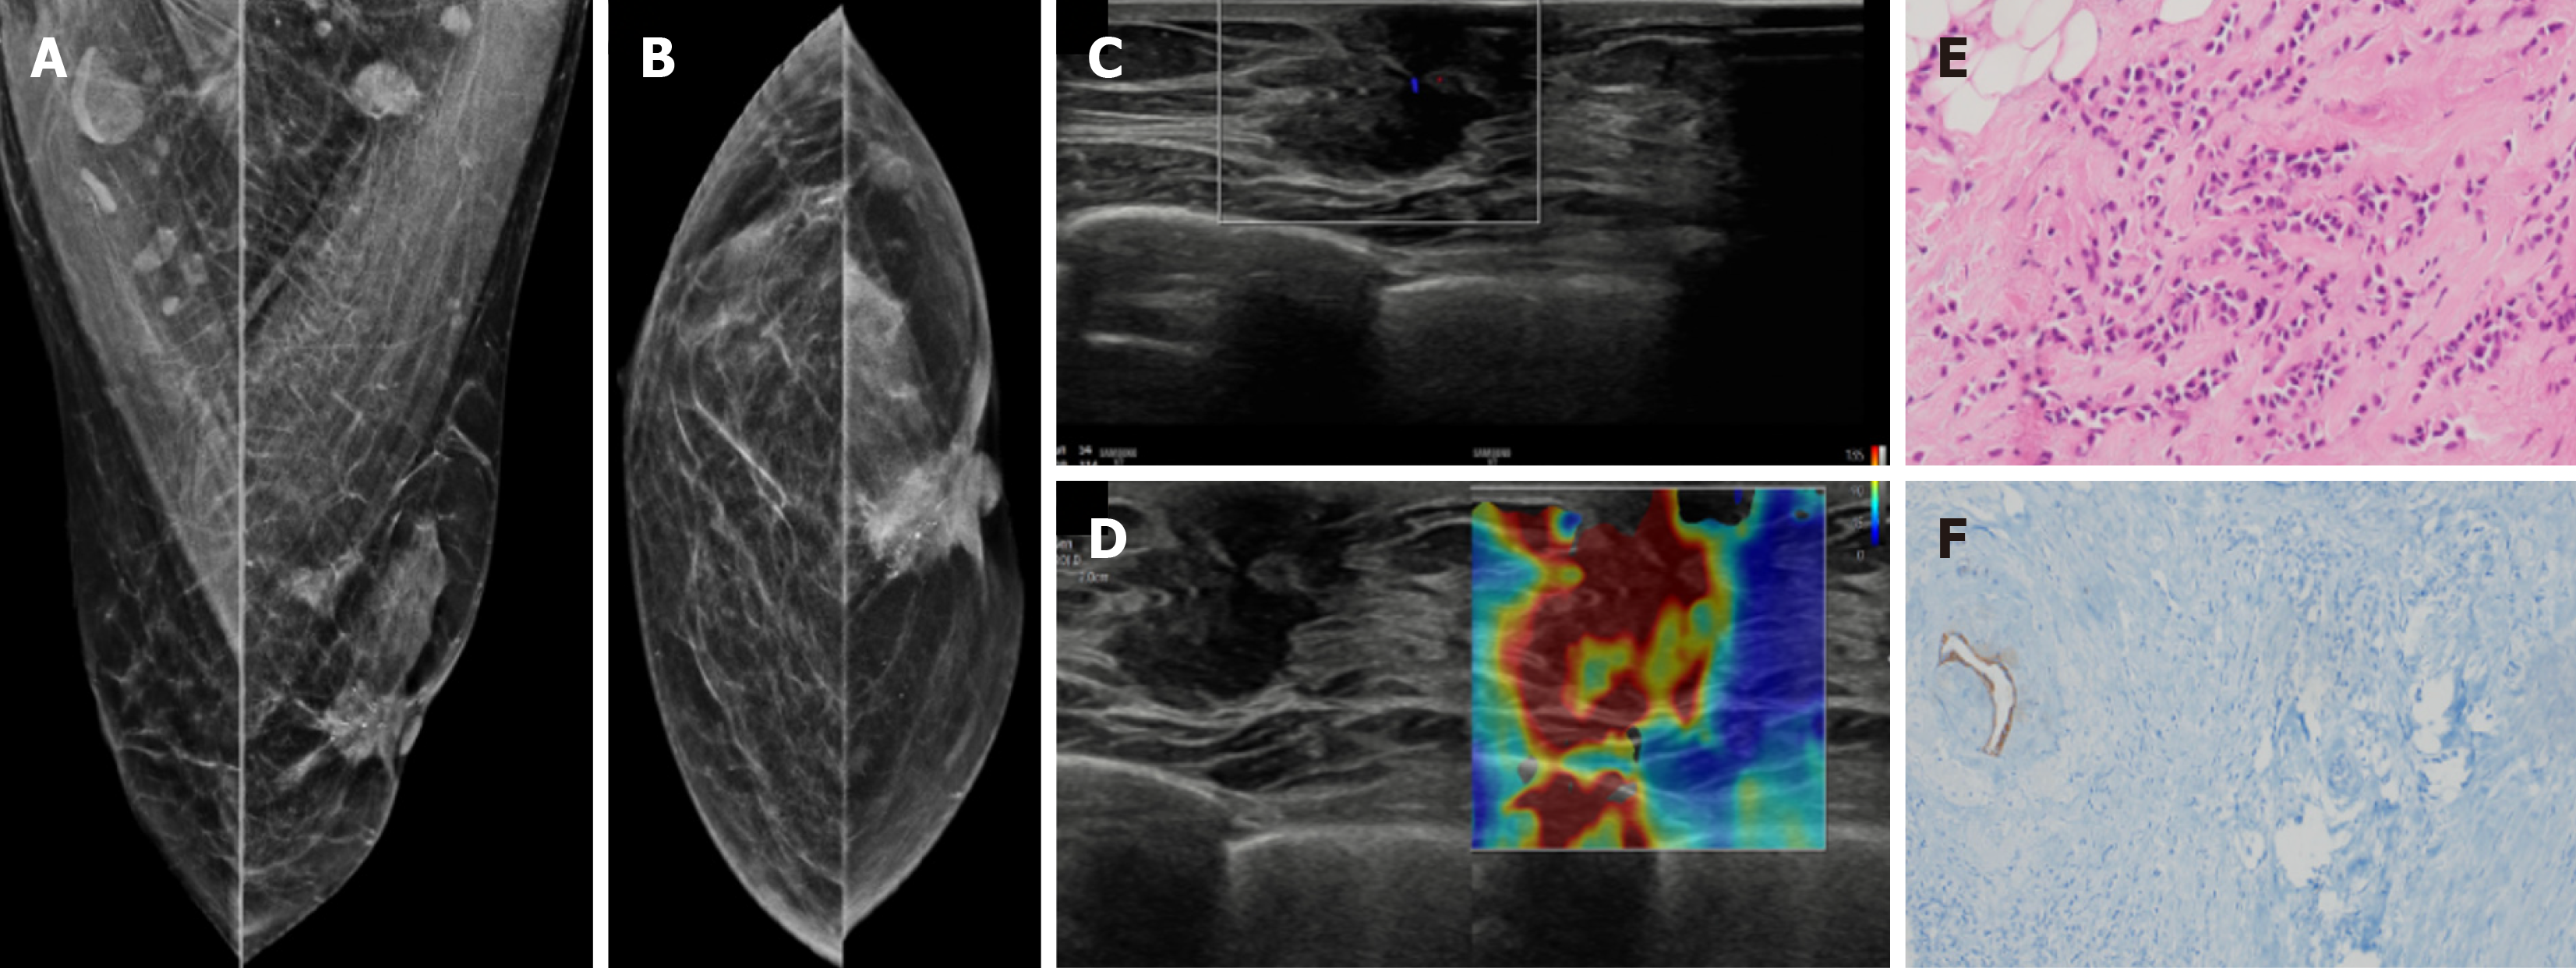

Figure 20  Invasive lobular carcinoma in a 65-year-old male with a hard retroareolar lump.

A: Mediolateral oblique; B: Craniocaudal mammography views showing an irregular high-density mass with spiculated margins, few punctate calcific foci and surrounding architectural distortion. Nipple retraction and overlying skin thickening are also observed; C: Ultrasound; D: Elastography images show an irregular mass with angular margins, which appears hard on elastography; E: Histopathology (hematoxylin and eosin, × 40); F: E-cadherin images show medium to small dyscohesive cells that lack E-cadherin expression.